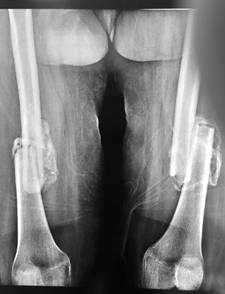

При поступлении пациентка находится в лежачем положении, при попытке вставания на ноги резкие болевые ощущения в области обеих бедер. При осмотре определяются комбинированные контрактуры обоих коленных (сгибание ограничено до 100°, разгибание до 160°) и голеностопных суставов (подошвенное сгибание ограничено до 100°, тыльное сгибание до 90°), патологическая подвижность в области обеих бедер. На рентгенограммах определяются консолидирующиеся в порочном положении переломы обеих бедренных костей с выраженным смещением отломков по длине и консолидированный в порочном положении перелом левой плечевой кости (Рис. 1,2). Разница в длине нижних конечностей составила 3 см.

Рис.1. Рентгенограмма пациентки С., 25 лет, на момент поступления

Рис.2. Рентгенограмма пациентки С., 25 лет, на момент поступления